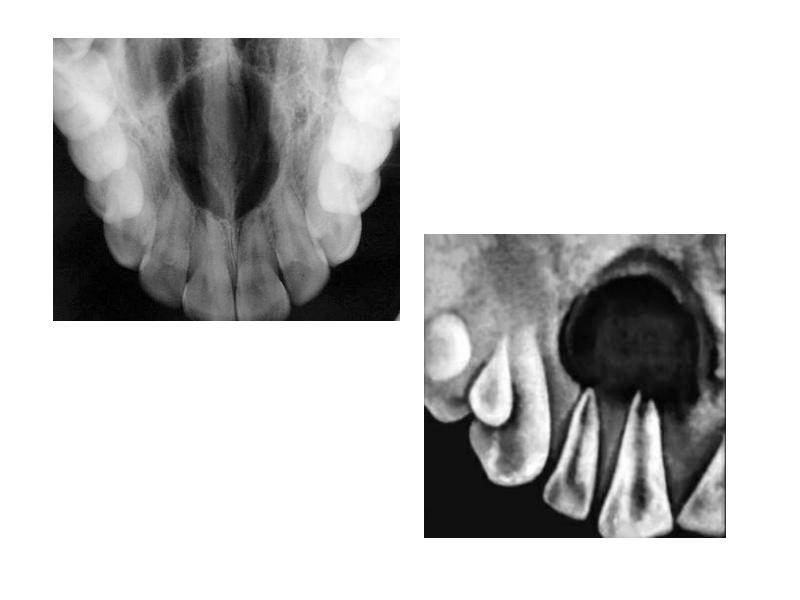

- 43. Радикулярная киста Образуется в альвеолярных отростках челюстных костей при прогрессировании хронического

- 45. Макроскопическая картина Увеличивается медленно (месяцы, а иногда годы), достигая размеров от

- 50. Фолликулярная киста (зубосодержащая) Является дизонтогенетической кистой, развивается из эмалевого органа непрорезавшегося

- 52. Микроскопическая картина Тонкий неороговевающий сквамозный эпителий выстилает внутреннюю поверхность кисты

- 54. Киста прорезывания Разновидность фолликулярной кисты (фолликулярная киста, связанная с коронкой прорезывающегося